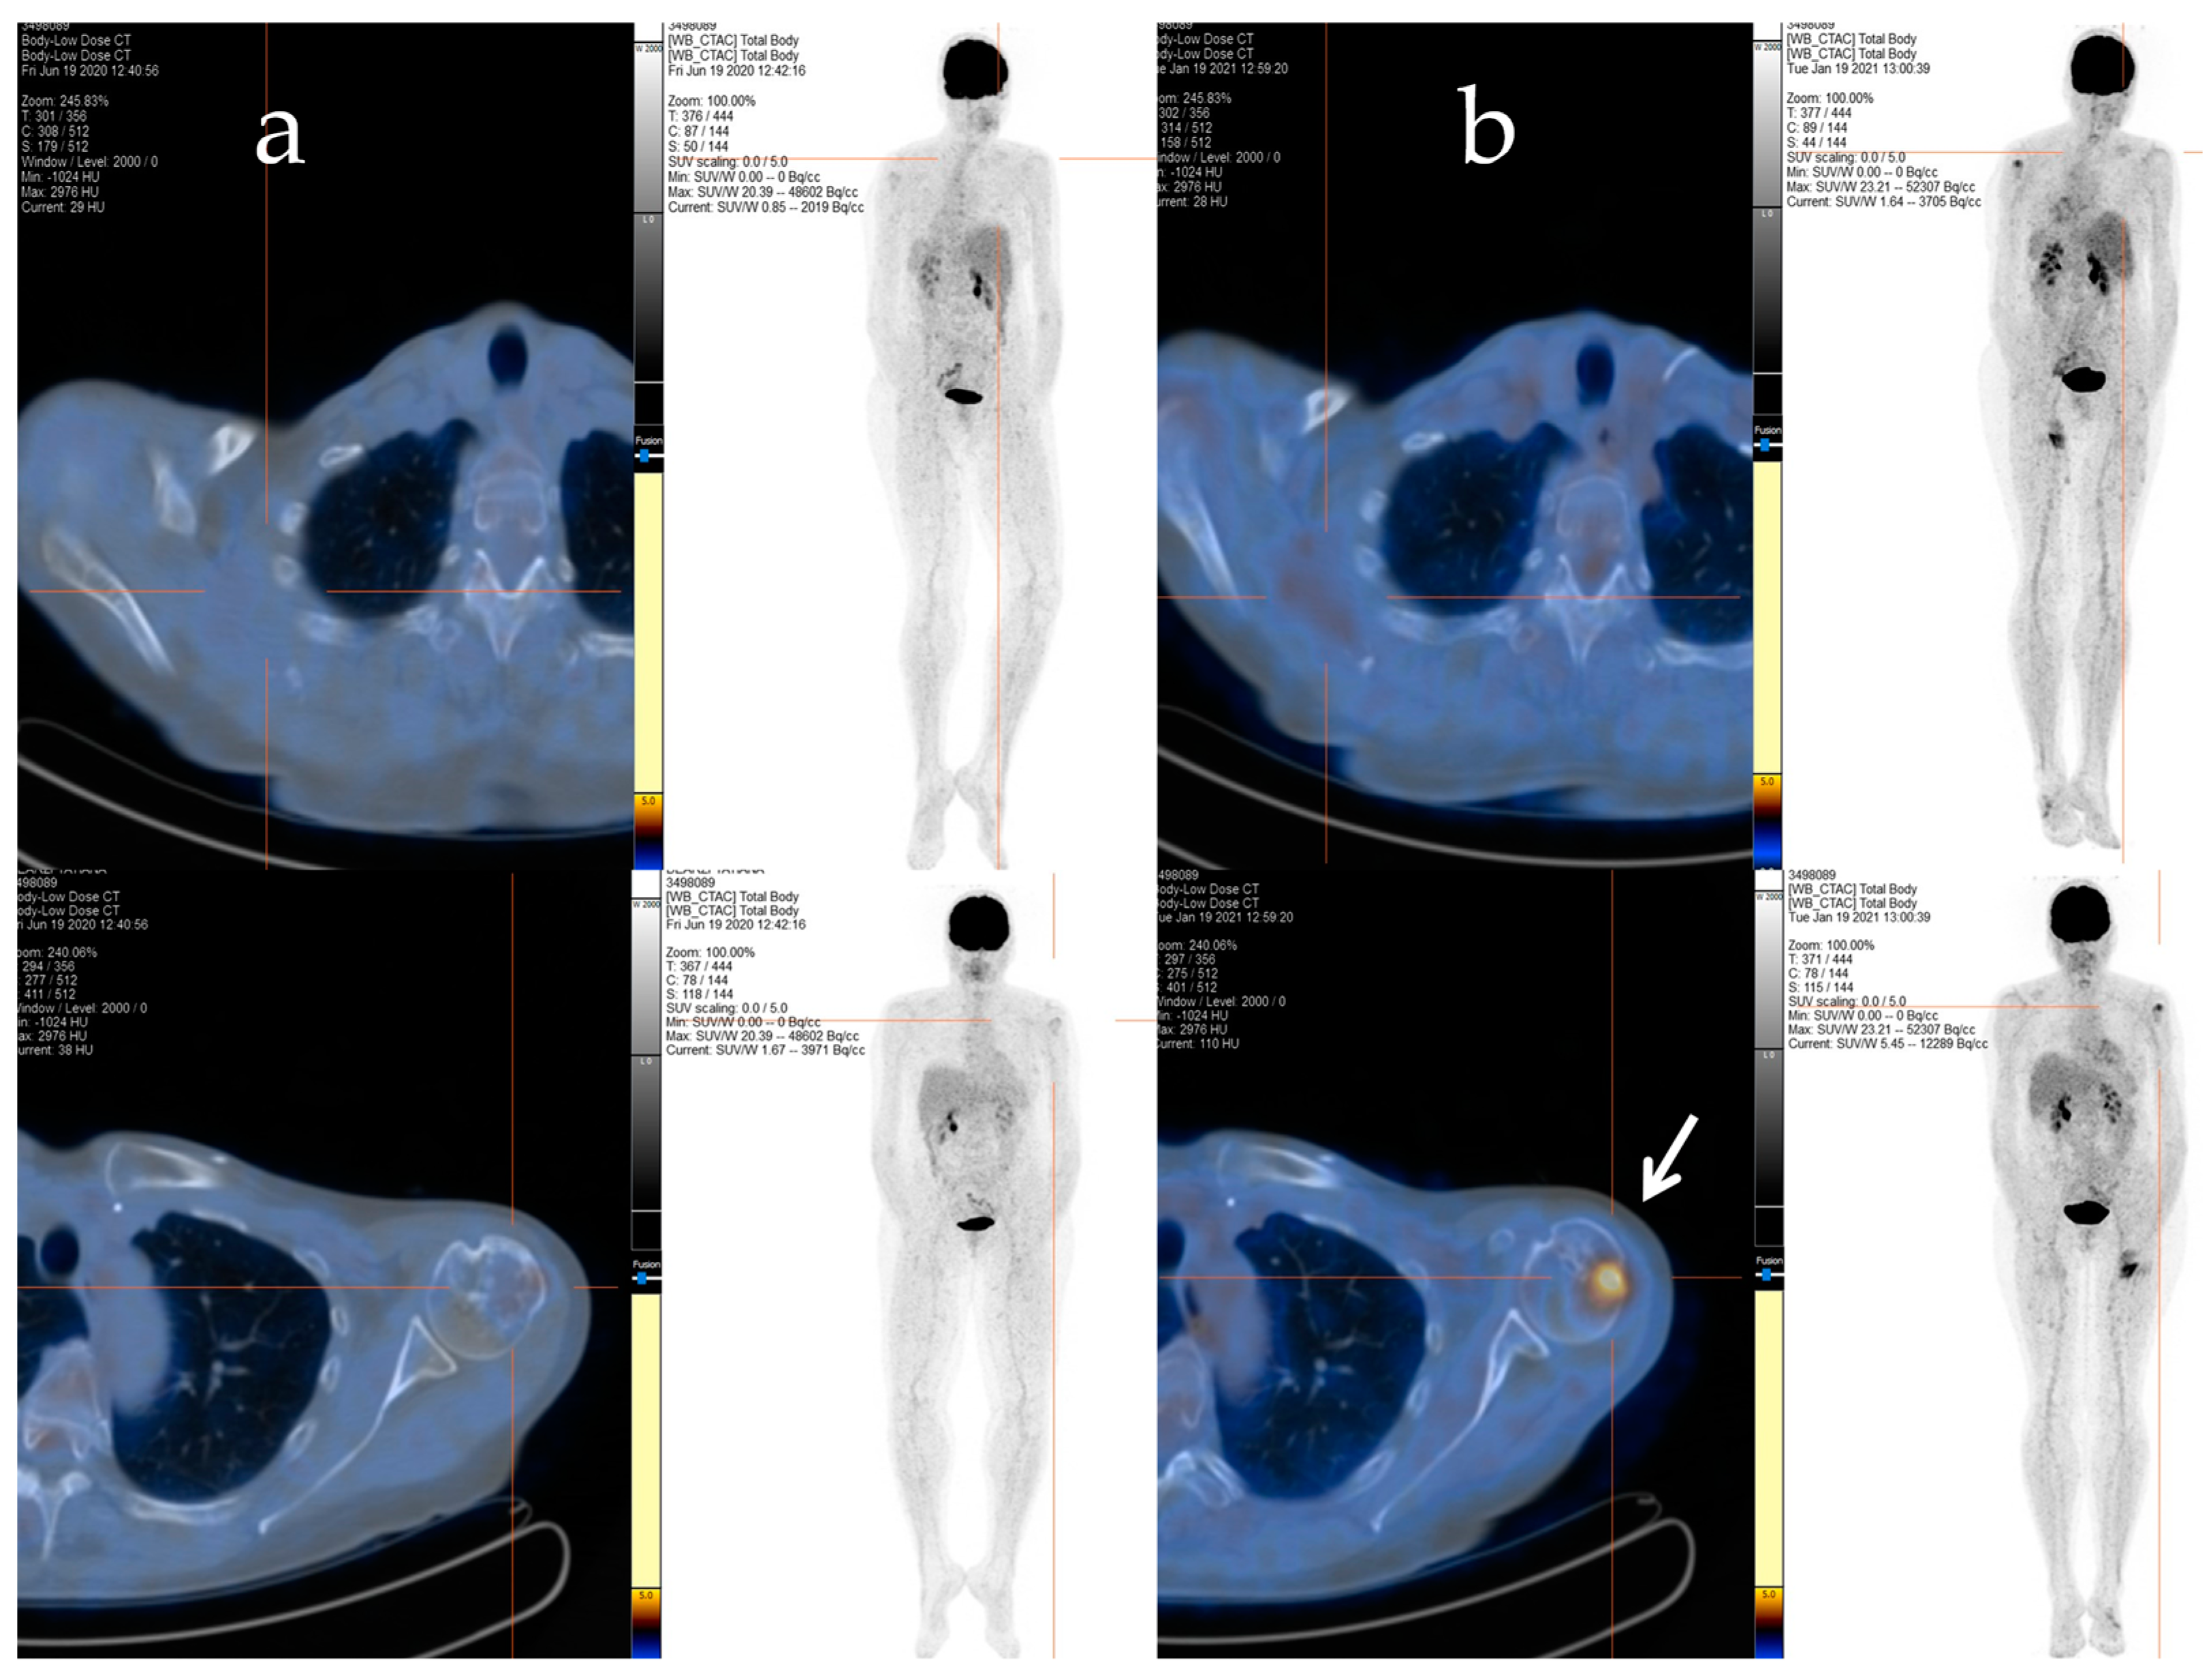

Afterwards, radiation therapy to the cervical segment (C4–C6) and left humerus (20 Gy/5 fractions) was performed, and a chemotherapy regimen consisting of epirubicin and ifosfamide was started. Despite an initial positive response after six cycles of treatment, signs of bone and soft tissue progression were apparent three months after the chemotherapy ended. Thus, the patient received a second-line treatment with trabectedin (1.5 mg/m2 q21), which was administered as a 24 h infusion every 3 weeks. After 48 cycles of treatment, despite the stable disease, the patient decided to discontinue the treatment due to severe fatigue, and a close follow-up was started. The patient maintained stable disease until January 2021 when a PET/CT scan revealed an increased uptake in the left proximal humerus (Figure 2a,b), right scapula, sternal manubrium, right iliac bone, and ipsilateral acetabulum.

Figure 2.

The F-18 FDG PET/CT performed after 48 cycles of trabectedin treatment (a) and after the period of trabectedin suspension (b). The main tumour lesions are indicated by white arrows.

With the rising of the disease, trabectedin treatment was resumed and continued for an additional 21 cycles until January 2022, when a PET/CT scan revealed a slight metabolic progression in the left humeral head. Thus, in March 2022, radiotherapy treatment on the left humeral head was completed (20 Gy/5Fractions), and, considering the stable disease revealed in July 2022, the trabectedin administration was continued until February 2023 (Figure 3).